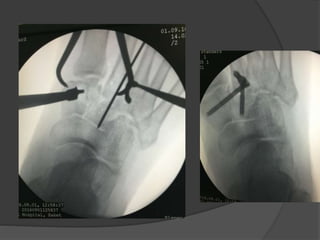

Case 1: A“healthy” 50 year old

Fell off a 3 ft high parapet

c/o pain, inability to bear weight on the right

foot

Initial radiographs

6 weeks later the cast was taken off, unable to bear

weight

Diagnosis

?

Lisfranc fracture- dislocation

Bony or ligamentous injury involving the tarsometatarsal

joint complex

Case 1: A“healthy”50 year old Fell off a 3 ft high parapet c/o pain, inability to bear weight on the right foot

• 71.

• 72.

6 weeks laterthe cast was taken off, unable to bear weight Diagnosis ?

• 73.

• 74.

Bony or ligamentousinjury involving the tarsometatarsal joint complex

• 77.